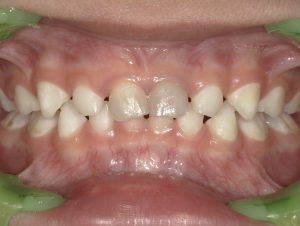

1. 歯の色の変化

最も分かりやすいサインの一つです。神経が死んで時間が経つと、歯の内部で壊死した血液の成分が変化し、歯の色が灰色、茶色、または黒っぽい色に変色します。特に前歯で目立ちやすい症状です。